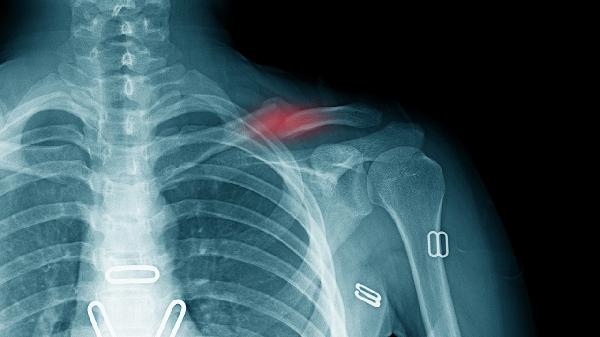

肩部直接撞擊、跌倒時(shí)手臂撐地或運(yùn)動(dòng)損傷可能導(dǎo)致鎖骨骨膜、周?chē)g帶或肌肉拉傷,甚至鎖骨骨折。疼痛通常急性發(fā)作,伴有局部腫脹、瘀斑,關(guān)節(jié)活動(dòng)受限。急性期應(yīng)立即休息、冰敷患處,使用繃帶或吊帶固定制動(dòng)以減少進(jìn)一步損傷。若疼痛劇烈或懷疑骨折,須及時(shí)就醫(yī)進(jìn)行X光檢查。

暴力外傷是鎖骨骨折主因,骨折端移位可能刺激周?chē)窠?jīng)血管,引起劇烈疼痛、畸形和骨摩擦感。確診需X光或CT檢查。無(wú)移位骨折可用鎖骨帶固定4-6周;移位明顯或開(kāi)放性骨折需手術(shù)復(fù)位,如鋼板內(nèi)固定術(shù),術(shù)后配合漸進(jìn)式康復(fù)訓(xùn)練恢復(fù)關(guān)節(jié)功能。